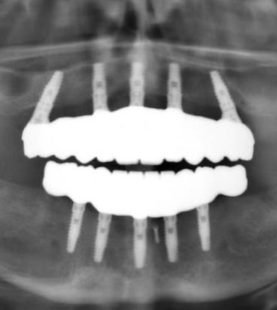

- Full Arch

- Understand the Fundamentals of Implant Dentistry:Gain a comprehensive understanding of the key concepts of implant dentistry, including patient selection, surgical anatomy, and tissue handling, essential for safe and predictable implant placement.

- Master Implant Surgery Protocols:Learn the step-by-step procedures for proper drilling protocols and implant placement, emphasizing the importance of precision and technique in achieving optimal results.

- Enhance Diagnostic and Planning Skills:Learn how to utilize diagnostic tools such as CBCT and intraoral scanning to create detailed implant treatment plans, ensuring precision in implant placement and restoration.

- Prepare for Full-Spectrum Implantology Practice:Develop the confidence and skills to plan, place, and restore dental implants within a clinical setting, while also gaining insights into the roles of auxiliary team members in supporting implant procedures.